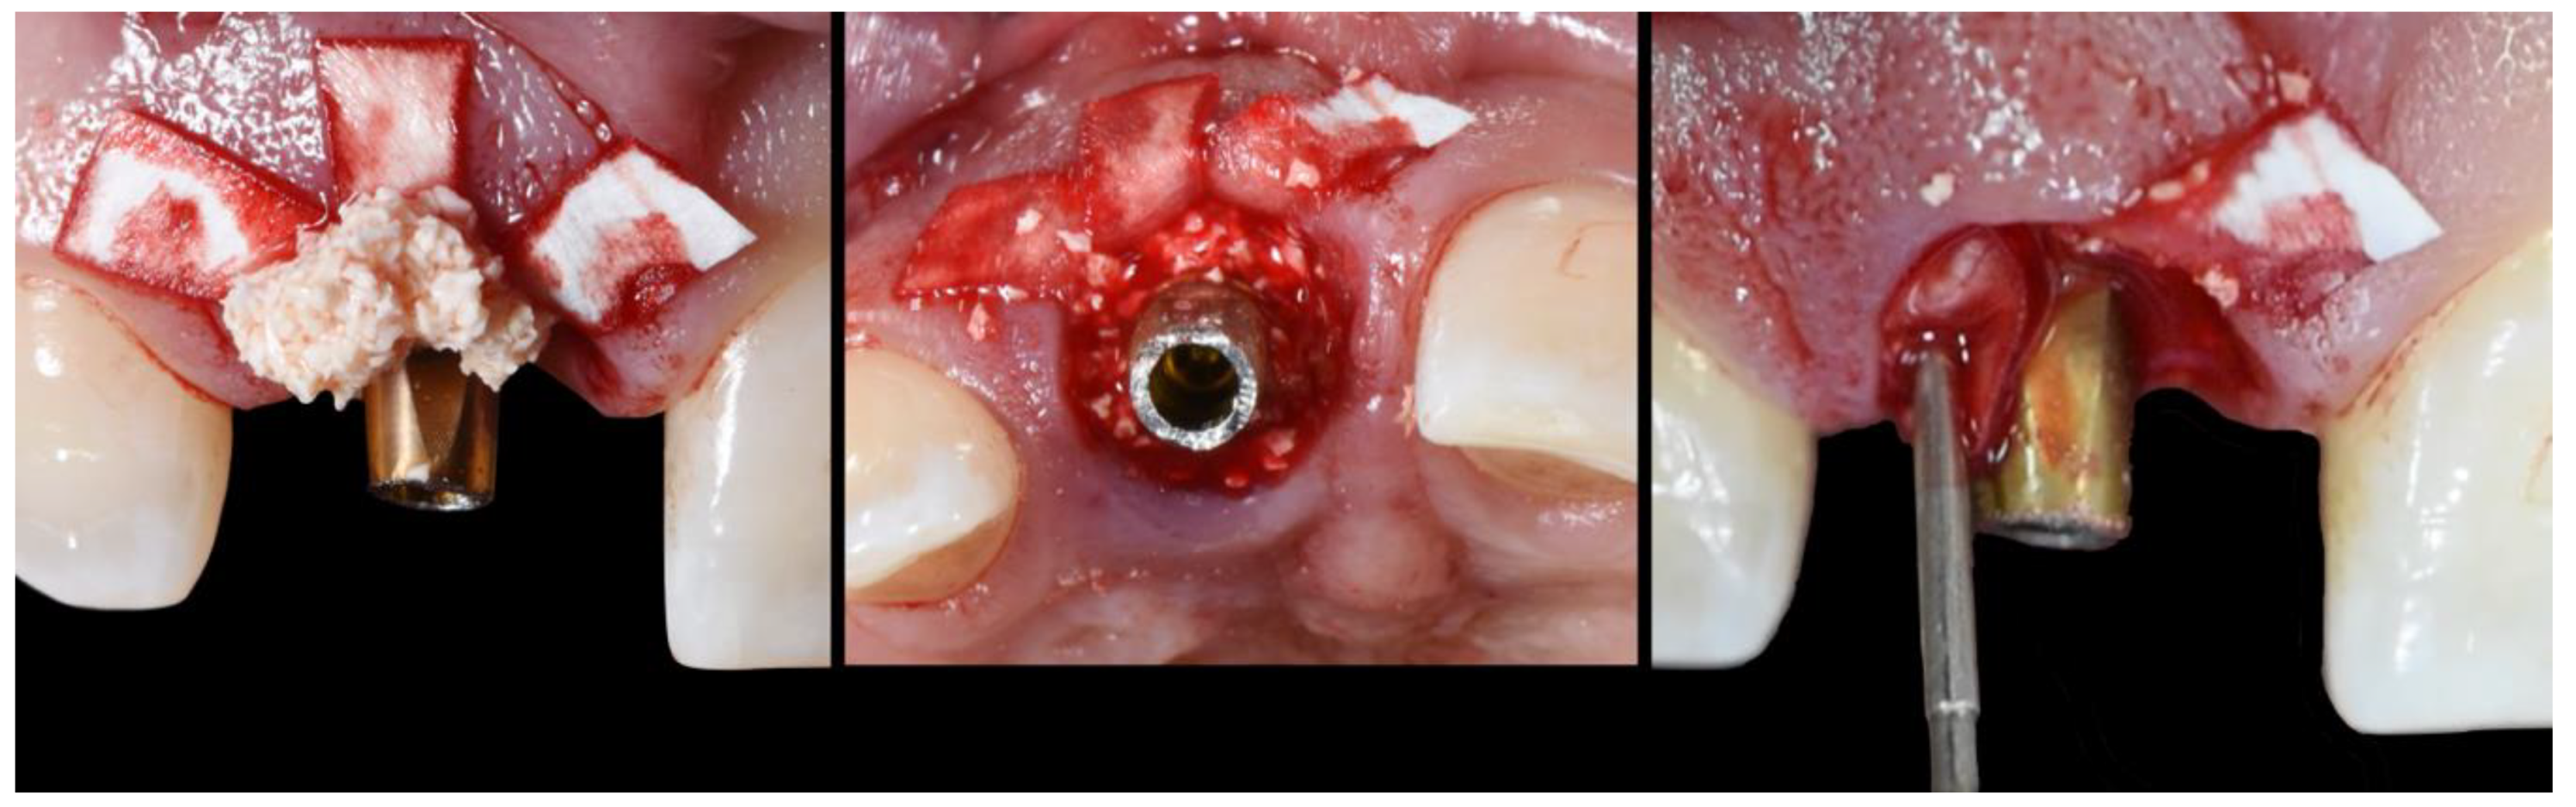

- (E)

- Bone replacement graft BRG introduction into the available space present within the socket, occupying both the soft and hard tissue zones present below the abutment’s shoulder.

- (F)

- Membrane adaptation and suturing with vertical mattress sutures.

- (G)

- Temporary prosthesis delivery, where the cervical margin is located supra-gingivally and comprises a 90′ emergence angle in relation to the abutment.

- (A)

- Supra-periosteal pouch design, demonstrating proper lateral and vertical extensions. The red lines demonstrate the pouch, while the yellow line demonstrates the mucogingival junction.

- (B)

- First abutment in place and membrane adaptation prior to BRG introduction.

- (C)

- Final relationship between first temporary prosthesis, abutment, and cervical gingival tissue.